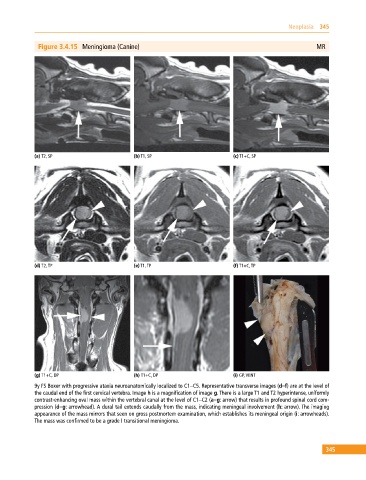

Figure 3.4.15 Meningioma (Canine) MR

(a) T2, SP (b) T1, SP (c) T1+C, SP

(d) T2, TP (e) T1, TP (f) T1+C, TP

(g) T1+C, DP (h) T1+C, DP (i) GP, VENT

9y FS Boxer with progressive ataxia neuroanatomically localized to C1–C5. Representative transverse images (d–f) are at the level of

the caudal end of the first cervical vertebra. Image h is a magnification of image g. There is a large T1 and T2 hyperintense, uniformly

contrast‐enhancing oval mass within the vertebral canal at the level of C1–C2 (a–g: arrow) that results in profound spinal cord com

pression (d–g: arrowhead). A dural tail extends caudally from the mass, indicating meningeal involvement (h: arrow). The imaging

appearance of the mass mirrors that seen on gross postmortem examination, which establishes its meningeal origin (i: arrowheads).

The mass was confirmed to be a grade I transitional meningioma.